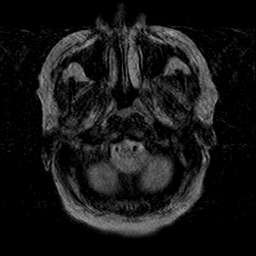

Cerebral hemorrhage, MR Study mr-t2 -- Slice #3

[Home][Help][Clinical] Slice 3